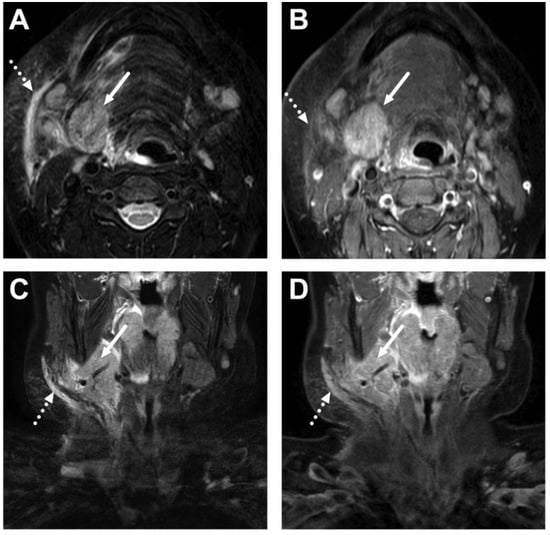

6.2. Venous Thrombosis